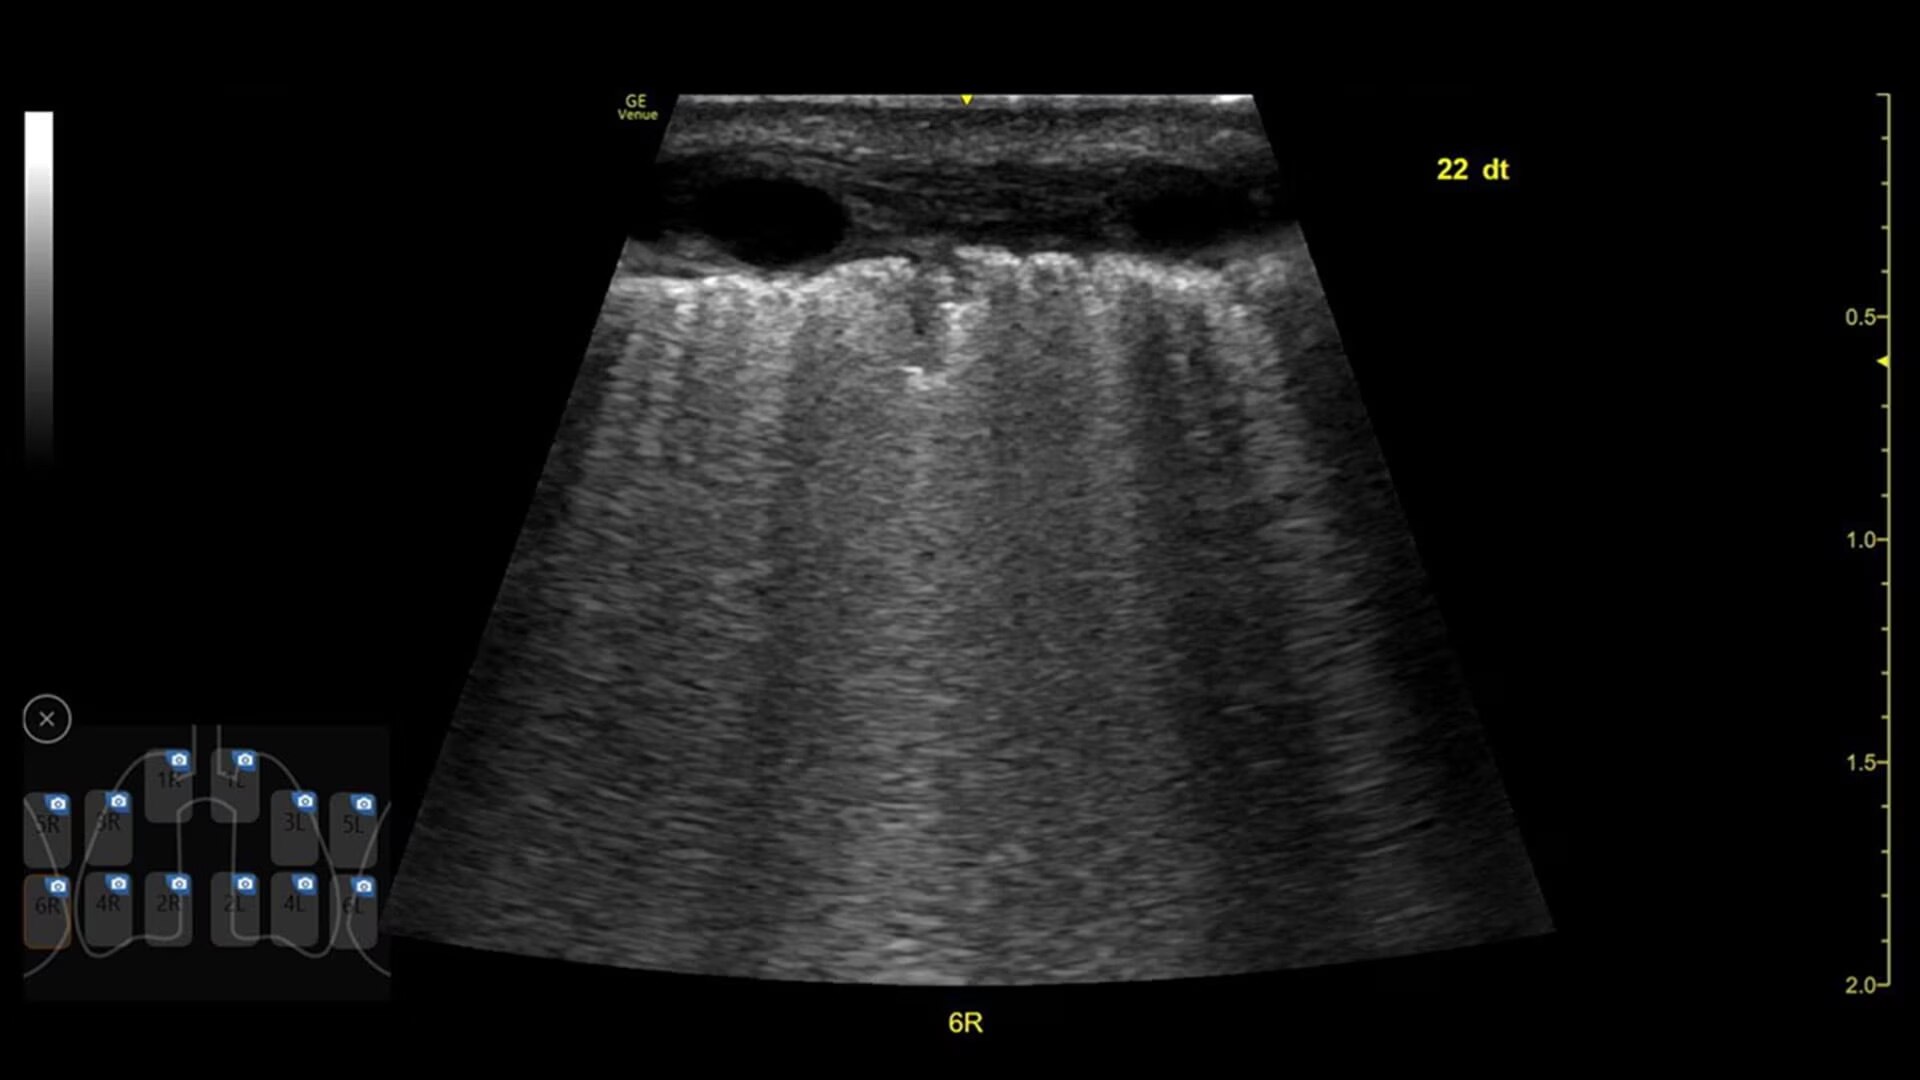

Visualize the entire lung with Lung Sweep

Lung Sweep provides a dynamic panoramic view of the entire lung. It activates when the probe taps the body and deactivates when the probe is lifted, so there’s no need to touch the screen.